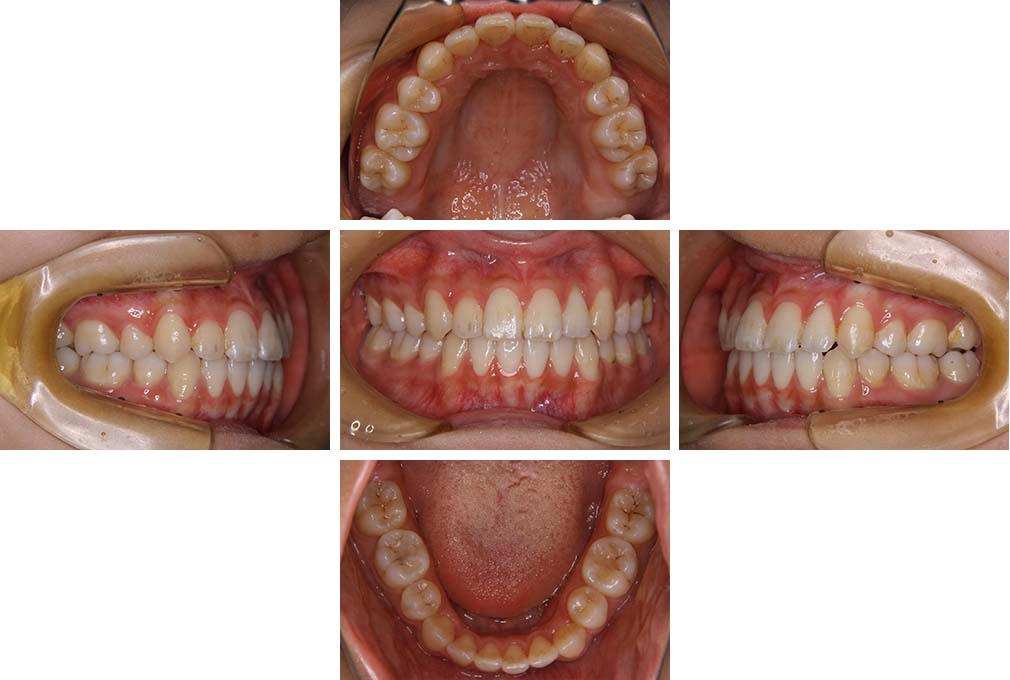

CASE:03

上下顎前突

初診時年齢 18歳4か月

性別 男性

治療費の目安 105万円程度(治療開始時)

歯列の乱れは著しくなく上顎右側側切歯が捻転し口蓋側へ転位していた。また、問診の中で患者さんから最も重視する治療結果として口元の突出の改善の申出があった。下顎が後退した上顎前突傾向ではあったが著しいものではなかった。上下顎前突と診断し上下顎小臼歯抜歯を行っていただき、上下顎舌側マルチブラケット装置を使用して、矯正用アンカースクリューを併用して動的治療を行った。上下顎前歯の後退を十分行い口元の突出感も改善した。治療後10年1か月の来院時には口元の突出感が再発することもなく、下顎前歯の少しの唇舌的なずれはあったが歯列は安定していた。動的治療期間2年2ヵ月間。

治療前

18歳4ヵ月

治療後

動的治療期間2年2カ月間

20歳10か月

10年経過

動的治療終了後10年1カ月

30歳11か月